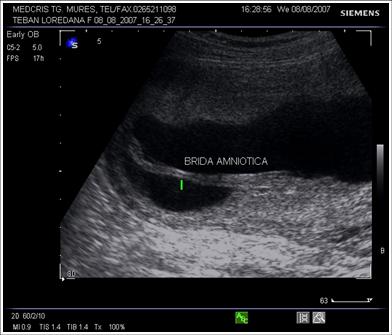

Benzi amniotice: linii ecogenice in lichidul amniotic intre

placenta si peretele uterin, unele produse de separarea partiala a amniosului

de chorion, altele produse de o sinechie uterina sau un sept uterin incomplet.

De obicei nu constrang miscarile fetale si nu sunt atasate fatului.

Fig. nr.226. Brida amniotica la o sarcina de 16 saptamini